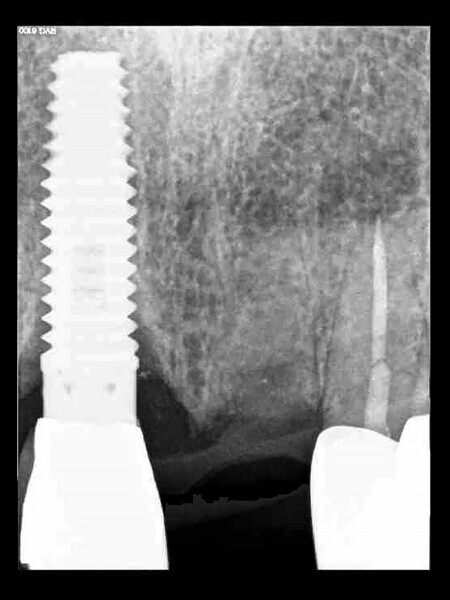

Fig. 13: The pre-op periapical radiograph revealed an existing implant-supported metal–ceramic restoration for the adjacent region #11.

Fig. 14a:

The CBCT cross-sectional image revealed a favourable pre-op condition for a PET procedure.